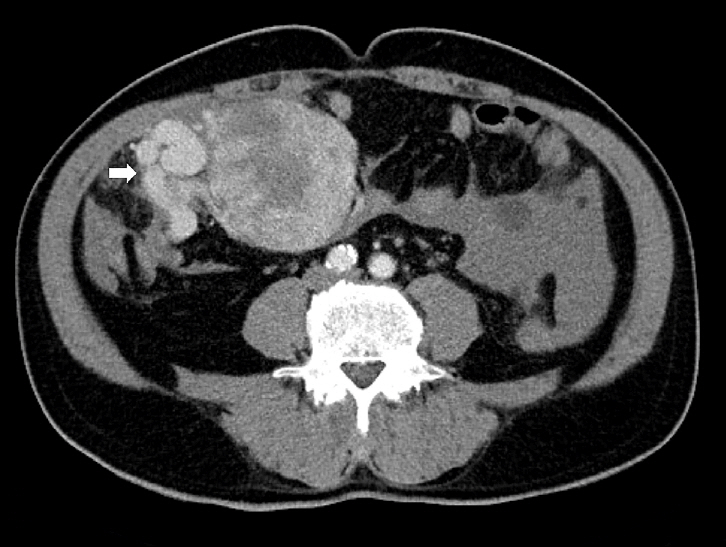

Upon imaging, SFTs typically show nonspecific radiographic features [60,61], whereas computed tomography (CT) usually yields a well-defined, occasionally lobulated, isodense mass relative to the skeletal muscle (Fig. 1). They exhibit heterogeneous contrast enhancement because of their rich vascularity [62,63]. Magnetic resonance imaging (MRI) typically shows intermediate T1 signal intensity and variable T2 signals, which correspond to fibrous (low T2) and cellular or myxoid (high T2) components [63-65]. Larger or more aggressive tumors may display heterogeneity because of fibrosis, necrosis, hemorrhage, or cystic changes [63].

In the thorax, SFTs are usually present as sharply marginated, pleural-based masses without chest wall invasion. Malignant lesions may exhibit increased fluorodeoxyglucose uptake on positron emission tomography; however, overlap with benign tumors may occur [66,67]. In the CNS, SFTs often mimic meningiomas on imaging. The lesions exhibit isointensity on T1-weighted MRI, variable T2 signals, and peripheral dural enhancement (dural tail); however, no specific CT or MRI features reliably distinguish them from other dural-based tumors [68,69].

Fig. 1.

Radiological findings of solitary fibrous tumor. Axial contrast-enhanced abdominal computed tomography demonstrates a large central abdominal mass. Prominent feeding vessels (arrow) are visible along the anterior aspect of the lesion.